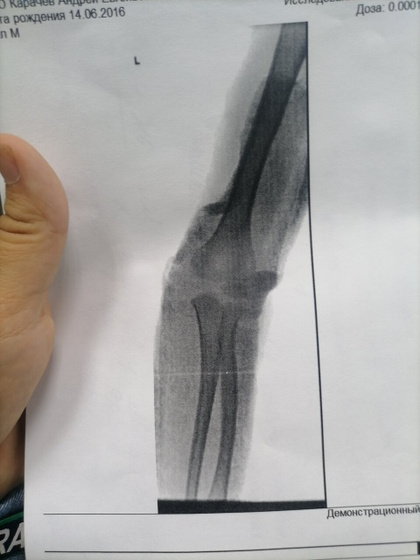

Сходили мы с переломом локтя 12 на прием, все было ок, гипс слегла помятый, сказали сходите на ренген и псм надо ли заменить его, сходили. Сказали все хорошо 29 приходите на снятие, ну мы спокойной и поехали домой, наступает 13,14 число и вот сегодня встаём все с утра и понимаем что гипс сломан в локте прям сгибе прямо, поехали мы с сыном в травму снова, пришли отправили к дежурному травмотологу осмотрел, спросил был ли 12 такой же он гипс? , я тип нет так не ходил, но был изломан внешне деформмрован, сказали не надо менять,отправили по итогу нас сразу поменять гипс, уехали мы домой. Сын встал рано, уснул в 3 часа где то дня, проспал 1.5ч - встал, пошли мы на улицу и он снова нам такой говорит смотрите снова качается гипс тип, мы такие в аху* как так то делают, даже сутки гипс не поддержался… Завтра поедет муж и скажет чтоб забинтовали не вот лангету на заднюю поверхность, а обмотали руку прям, 2 недели ходить ещё, не будем же ежедневно менять ездить его эту лангету.